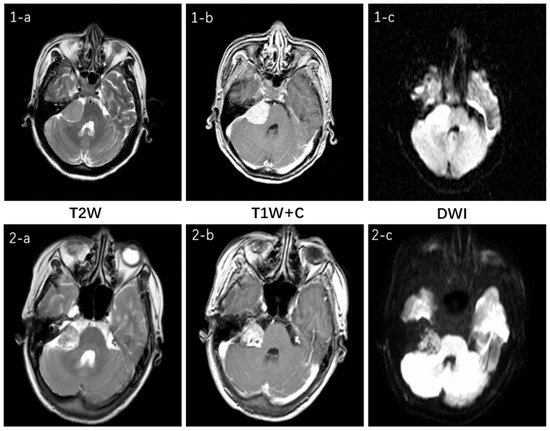

Figure 11 illustrates the multimodal MRI features for the two tumor types and their respective sequences involved in this study. Both tumors are located in the cerebellopontine angle and exhibit no significant difference. On T2W imaging, both demonstrate moderate signal intensity, which is slightly uneven in the VS. Both of the T1W + C sequences show a high signal and clear enhancement. In the DWI sequence, they appear isointense but with slight variations in signal intensity: the CPAM signal is relatively uniform, whereas the VS lesion signal is less so. Clinically, this represents only one manifestation of what can be variable presentations for the same tumor type, thereby increasing diagnostic challenges [27].

Figure 11.

The top row, 1, represents CPAM, while the bottom row, 2, represents VS. a is the T2W sequence, b is the T1W +C sequence, and c is the DWI sequence. In the T2W sequence, they both show a medium signal with VS having a slightly uneven signal inside the tumor; in the T1W + C sequence, both show a high signal and obvious enhancement; in the DWI sequence, both are isointense, with slightly different signal intensity inside the lesion, although CPAM(1-c) shows a relatively uniform signal while VS(2-c) has a slightly uneven signal inside the lesion.